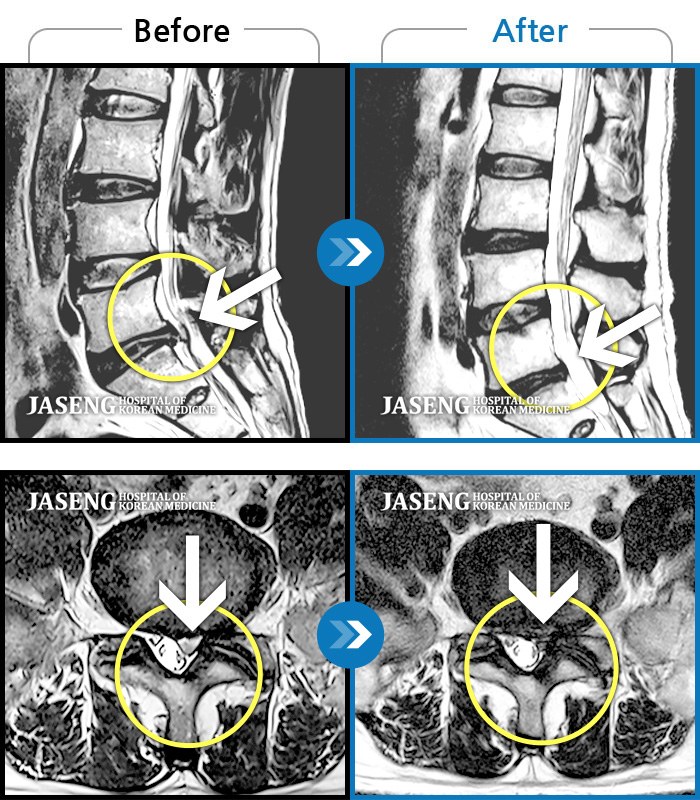

Before

After

환자에게 사전 동의를 받아 동일 조건에서 촬영되었습니다.

개인에 따라 치료 후 부작용이 발생할 수 있으니 의료진과 상담 후 치료를 진행하시기 바랍니다.

우측 엉치 부터 발 끝까지 저리고 아픈 증상이 있었다.

허리통증과 좌측 엉치 및 꼬리뼈 까지의 심한 통증으로 일상생활의 어려움 호소